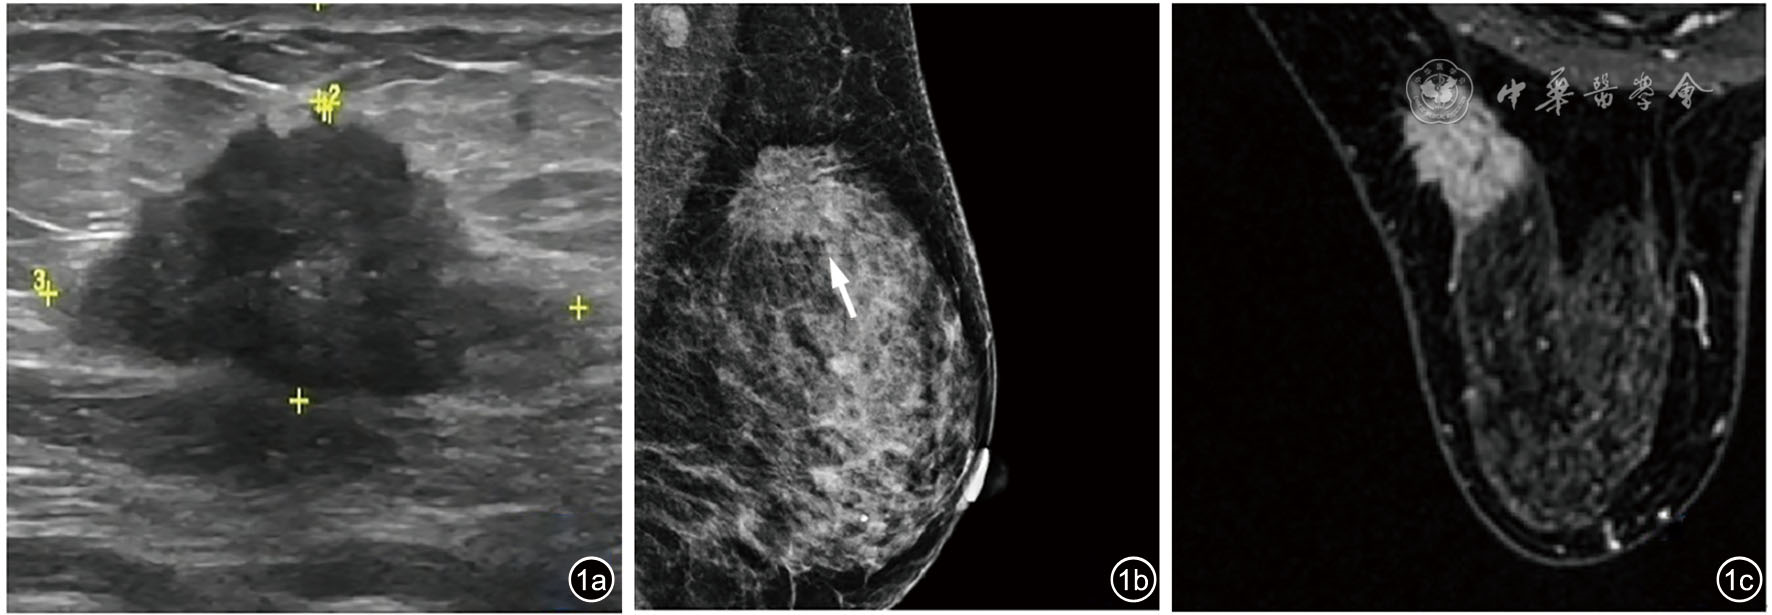

图1 肿块型乳腺病变不同影像学图像。女性,51岁,肿块型病变,病理结果为浸润性导管癌。图a为US提示左乳实性占位,BI-RADS 4C;图b为MG(MLO位)提示左乳外上占位,伴钙化(箭头),BI-RADS 4C;图c为MRI提示左乳外上象限占位,BI-RADS 4C 注:US为常规超声;BI-RADS为乳腺成像报告和数据系统;MG为乳腺X线摄影;MLO位为内外斜位;MRI为磁共振成像